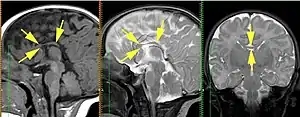

Агенезія мозолистого тіла (АМТ) — рідкісне вроджене захворювання, за якого спостерігається повна або часткова відсутність мозолистого тіла. АМТ може бути виявлене на МРТ, часто поєднується з різними вадами розвитку[1].

Діагностика порушення здійснюється внутрішньоутробно або після народження. Методи діагностики: УЗД, МРТ, КТ.

Основні діагностичні критерії, що дозволяють визначити наявність АМТ:

1) радіальний патерн борозен медіальної поверхні мозку — борозни медіальної поверхні гемісфер мозку відходять від даху III шлуночка, поясна звивина не сформована;

2) паралельність тіл бічних шлуночків;

3) відстань між тілами бічних шлуночків збільшена;

4) аномальне розширення задніх рогів бічних шлуночків;

5) відсутність прозорої перегородки;

6) високе розташування III шлуночка.